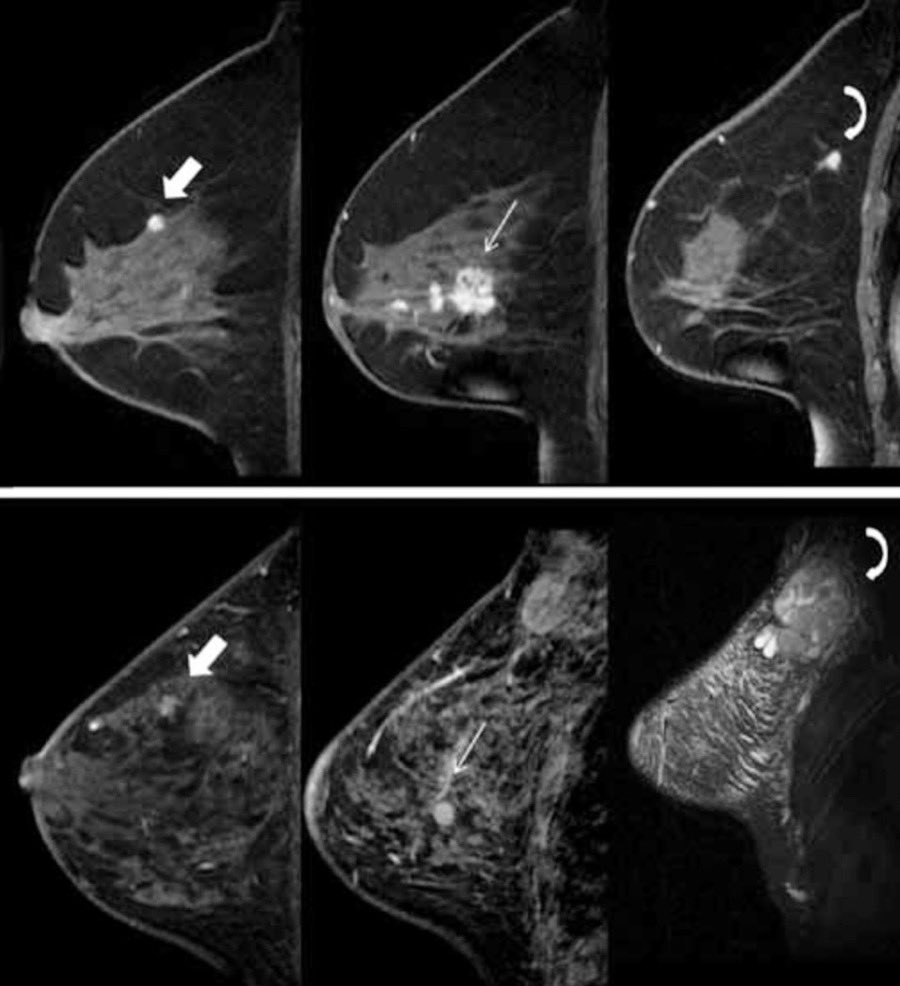

La RM mamaria es un examen que se hace para detectar cáncer de mama y otras anomalías de las mamas. También puede usarse con una mamografía como herramienta de detección prematura. Lleve sus revisiones de mama al día, adelantarse es la mejor forma de combate.

La RM mamaria es un examen que se hace para detectar cáncer de mama y otras anomalías de las mamas.

También puede usarse con una mamografía como herramienta de detección prematura.

Lleve sus revisiones de mama al día, adelantarse es la mejor forma de combate.